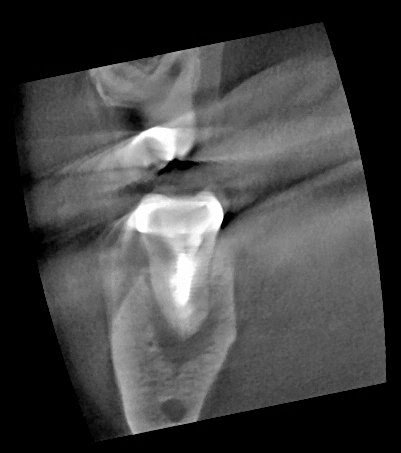

At this point, retreatment or surgery are the options to preserve the tooth. With a crown, not needing to be replaced, a long post and overfilled gutta percha – which can be difficult to retrieve, we considered a surgical approach. Since this is a second molar, the buccal bone is too thick to allow for conventional surgical approach (apicoectomy). After discussing risks of intentional replantation, pt elected to preserve tooth using intentional replantation.